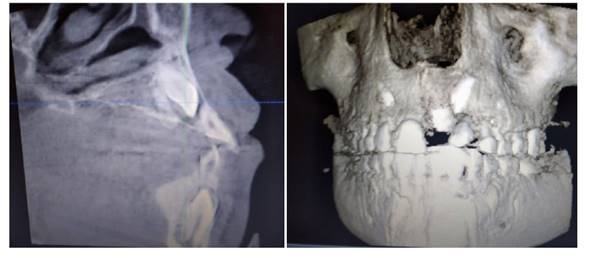

Acerca del plan de tratamiento, se hizo una propuesta multidisciplinaria conformada por un odontopediatra, un ortodoncista, un cirujano maxilofacial y un periodoncista. Las alternativas de tratamiento fueron las siguientes: 1) extracción de las UD 23 y 63, cerrar espacios con ortodoncia, sacrificando la UD 23 y haciendo tracción de la UD 21; 2) extraer el canino primario (UD 63), distalizar la UD 23 para una correcta ubicación y posterior tracción de la UD 21. Se escogió la última opción por la posibilidad de distalizar el canino y ubicarlo en posición sin eliminar otra unidad dentaria.

Inicialmente, se realizó la exodoncia del canino primario superior izquierdo para mejorar el corredor de erupción del incisivo central superior permanente. En la fase de ortodoncia inicial se coloca la aparatología fija con prescripción de Roth slot 0,22, exclusivamente en las UD 24, 25 y 26, además de un minitornillo como anclaje absoluto en la zona molar izquierda para tracción distal del canino superior (UD 23) y evitar así mesializaciones no deseadas al consolidar dicho sector. Al ubicar la UD 23 en su posición correcta, la UD 21 erupcionó posterior a destrabar ese espacio. Después de observar que dicha unidad dentaria iba erupcionando, se realizó un ojal quirúrgico y se cementó un bracket en la UD 21 y en el resto de la arcada superior para continuar con los pasos de alineación y nivelación, siguiendo la secuencia de arcos con normalidad en la ortodoncia correctiva (Figuras 4 y 5).